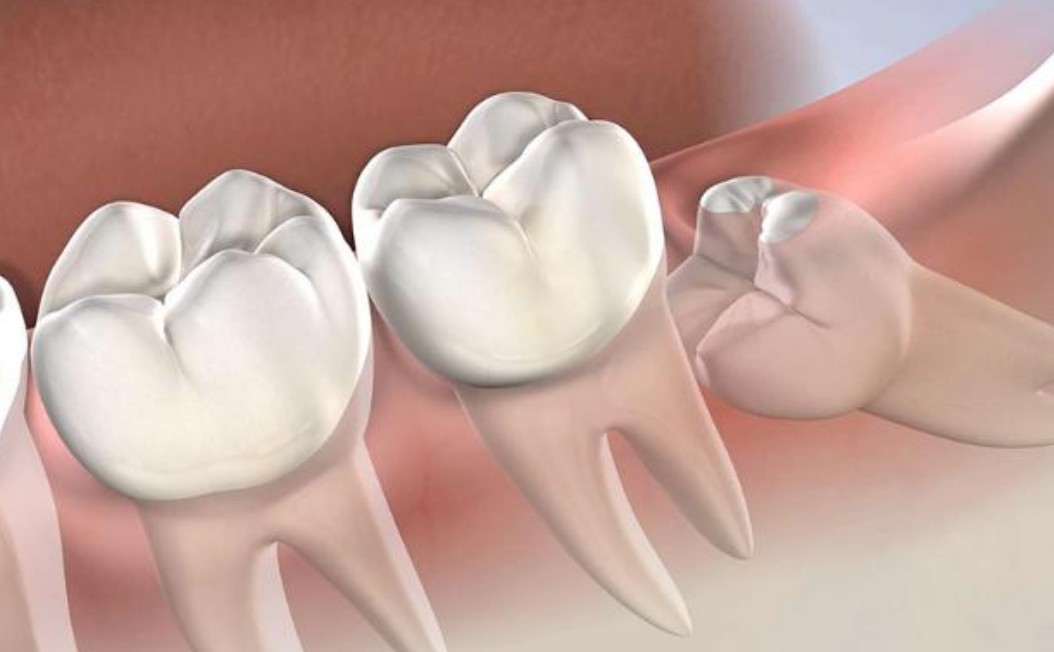

• Mọc nghiêng: răng khôn bị nghiêng vào răng số 7 hoặc ra ngoài má.

• Mọc ngang: răng khôn phát triển nằm ngang, không thể trồi lên khỏi nướu.

Răng khôn thường mọc sát răng số 7, chiếc răng chịu trách nhiệm chính trong việc nhai và nghiền thức ăn. Nếu răng khôn mọc lệch vào răng số 7, nó có thể làm tiêu chân răng, gây viêm tủy hoặc sâu răng kế cận.